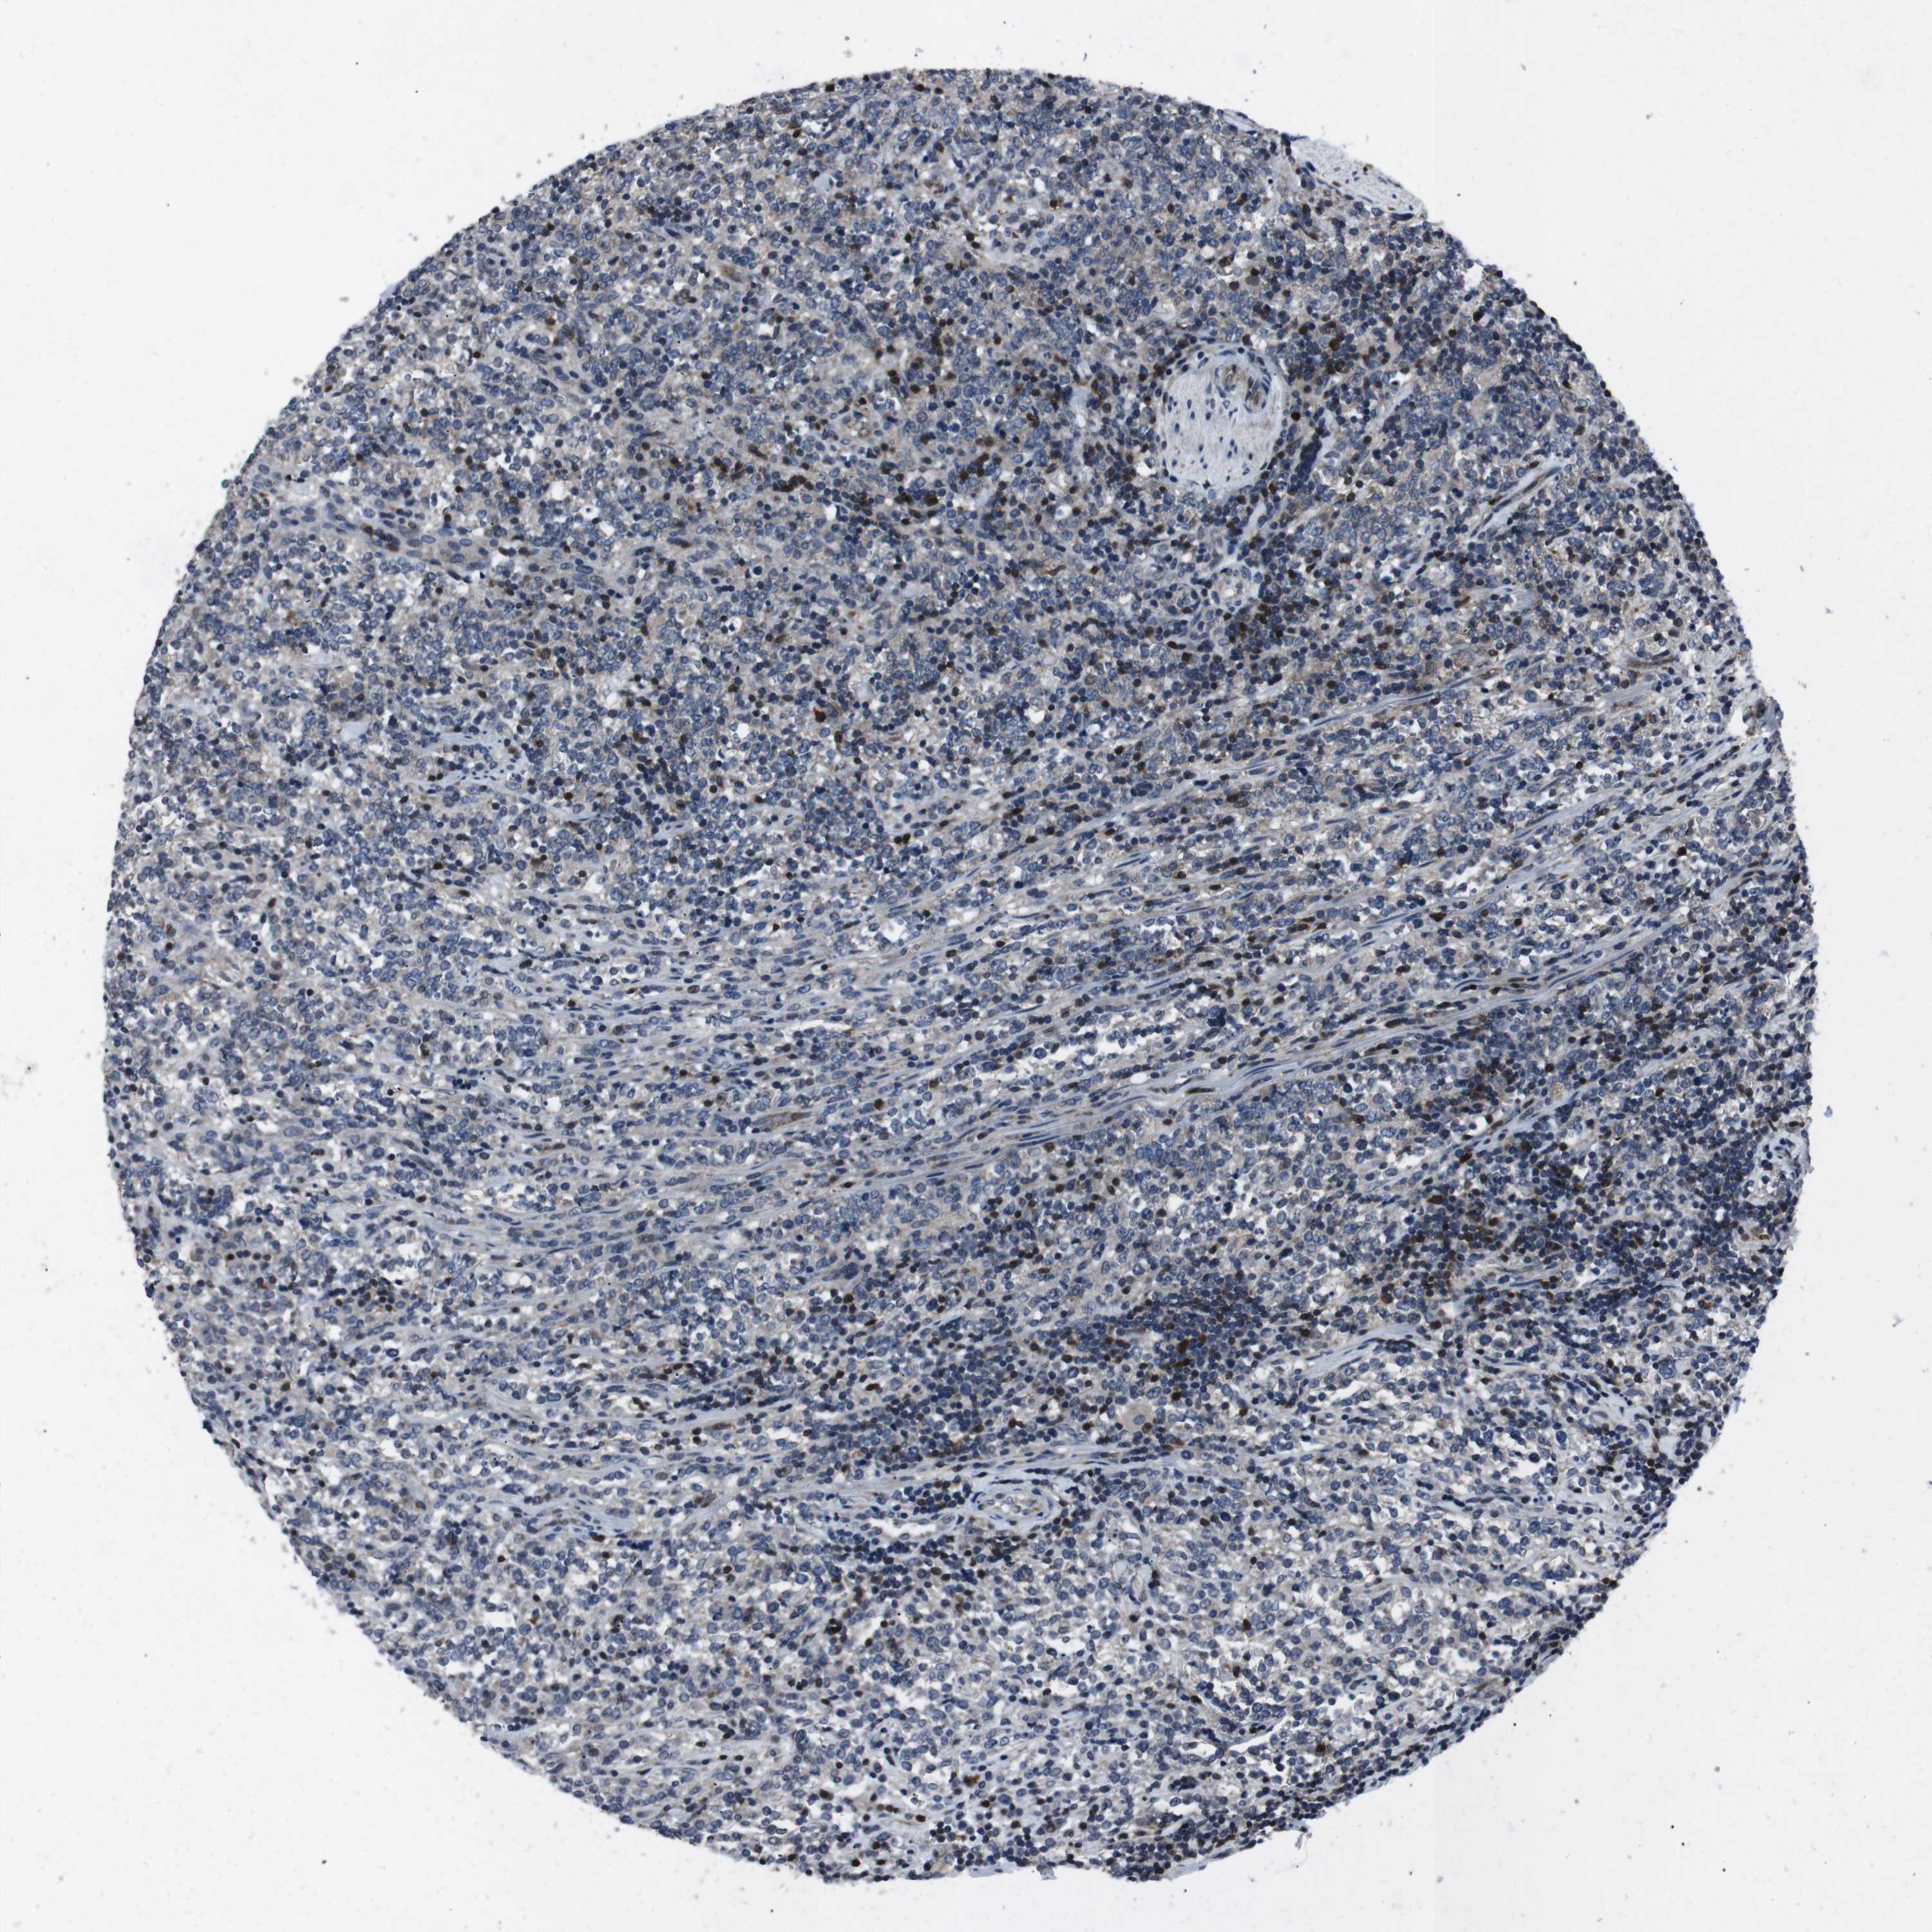

LYMPHOMA - Protein expressioni

A mouse-over function shows sample information and annotation data. Click on an image to view it in a full screen mode. Samples can be filtered based on level of antibody staining by selecting one or several of the following categories: high, medium, low and not detected. The assay and annotation is described here.

Antibody staining in the annotated cell types in the current human tissue is reported as not detected, low, medium, or high, based on conventional immunohistochemistry profiling in selected tissues. This score is based on the combination of the staining intensity and fraction of stained cells.

Each image is clickable and will lead to virtual microscopy that enables deeper exploration of all samples and also displays staining intensity scores, fraction scores and subcellular localization as well as patient and tissue information for each sample.

Antibody HPA001860

Antibody CAB013108

Malignant lymphoma, non-Hodgkin's type, High grade

Hodgkin's disease, NOS

Malignant lymphoma, non-Hodgkin's type, Low grade